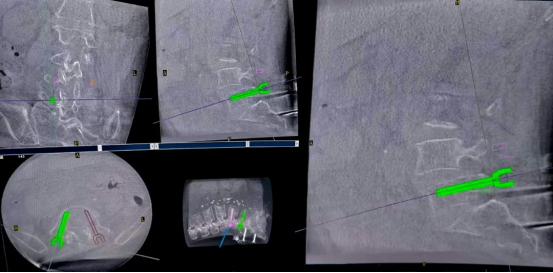

During the procedure, Perlove Medical's 3D C-armperformed a 3D scan of the lumbar spine., and the 3D images were then imported into the robotic work system. The surgeon used the system's software to observe the patient's lumbar anatomy (intervertebral disc height, vertebral body size) and identified the diseased segment (L4-L5). A comprehensive surgical plan was then developed, defining the optimal trajectory for screw placement (including angle, depth, and diameter) and the optimal size and position for the interbody cage, ensuring the plan was customized to the patient's individual anatomy.

Following the preplanned trajectory for screw placement, the surgeon made two small incisions (approximately 2–3 cm) on both sides of the affected spinal segment on the patient’s back. Through these incisions, dilators were inserted to gradually separate the subcutaneous tissue and muscles without cutting them. This process ultimately created a working channel with a diameter of only 3–4 cm, allowing precise access to the surgical segment. This technique maximizes the preservation of lumbar muscles and minimizes the risk of postoperative pain and functional weakening.

The robotic arm moved to the planned entry points, with its guide sleeve perfectly aligned with the pre-planned trajectory. The surgeon then drilled four Kirschner wires through this guide.